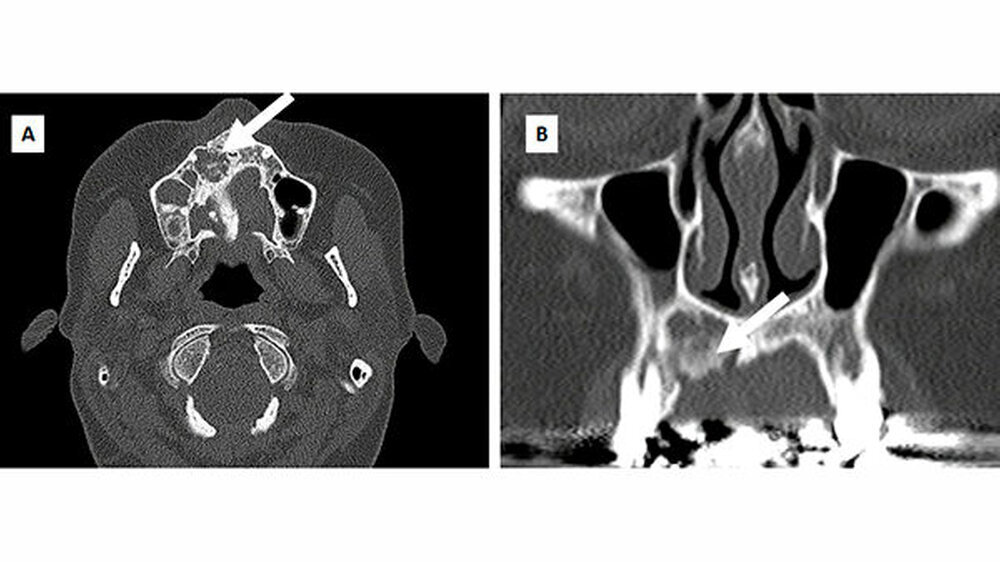

In der Panoramaschichtaufnahme zeigte sich eine Osteolyse im Bereich der Oberkieferfront Regio 12 (Abbildung 2), weshalb eine 3-D-Bildgebung zur Größenbestimmung durchgeführt wurde. Die durchgeführte CT-Diagnostik ergab den Nachweis eines Os librum mit den Maßen 7 x 8 x 11 mm unter Beteiligung der beiden Pfeilerzähne 11 und 13 (Abbildung 3).